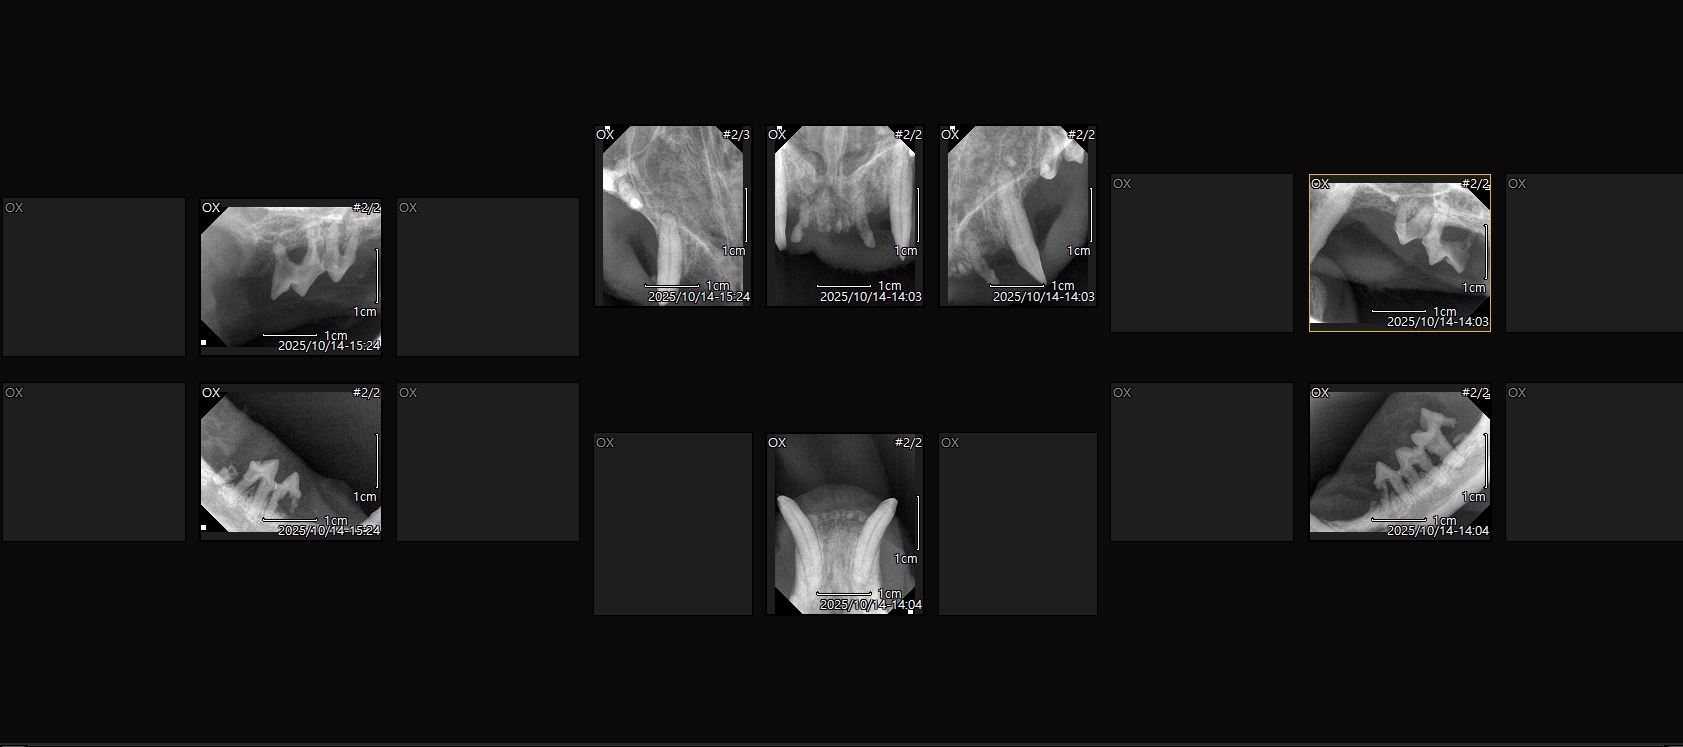

| 대상묘 병명 | 칼리시에 의한 만성 구내염 |

| 치료과정 | 14일 치과치료 예약을 잡고 13일 퇴근하고 아이를 포획하러 갔습니다 그날은 가을비가 내리던 날이었어요 비가 와서 오늘은 포획을 포기할까도 싶었지만 그렇게 되면 병원예약에 맞춰서 다시 예약을 해야하는데 이러다간 구조가 늦어질것같아서 일단 시도를 했습니다 포획틀을 설치하고 방수커버를 씌운뒤 멀찌기 떨어져서 기다렸습니다 빗줄기가 거셀땐 차밑에서 나오질 않았고 주춤해지면 나와서 주변만 맴돌았어요 비는 오고 시간은 흐르고 날은 어두워지고 제 마음은 정말 타들어가게 조바심이 났습니다 이대로 실패하나 철수할까.. 그래도 조금만 더 기다려보자 하여 1시간을 넘게 서로 비에 젖어가며 대치하다 겨우 구조에 성공, 바로 동물병원으로 데려가서 입원을 시키고 다음날 원장님께서 출근하셔서 수술에 필요한 검사를 하시고 건강상 큰 이상이 없다 판단하여 바로 전발치 수술과 중성화 수술을 같이 했습니다 pcr결과 칼리시가 발견되었고 칼리시에 의한 구내염으로 진단을 내리셨고 목구멍에도 염증이 많아서 며칠 수액을 맞았습니다 칼리시로 인한 구내염이라 완치가 될진 지켜보는수밖에 없다 하셨어요 수술하고 난 뒤 상태는 어떤지 검사를 해야하는데 아이가 생각보다 경계심이 많아서 어쩔수없이 살짝 재우고 검사 및 인터페론 주사처치를 했고 그 후로는 경계심도 조금씩 줄어들고 크게 아파하거나 불편해하지 않고 밥도 잘 먹는다해서 수액은 제거하고 입원만 진행했습니다 저희집에서는 케어를 해줄수없어 병원에 2주 조금안되게 입원하면서 중간중간 체크도 해주시고 컨디션이 어느정도 좋아졌을땐 예방접종도 한차례 진행했습니다 넥카라 때문인지 목구멍 염증 때문인지 수술하고 얼마 지나지 않아서인지 여전히 입가에 조금씩 침이 맺혀있긴 했어요 병원에서도 봐주시긴 했지만 중간중간 제가 가서 먹을거 먹는 모습도 보면서 원장님과 상의후 퇴원 날짜를 정했습니다 |

| 대상묘 치료중 사진 |      |